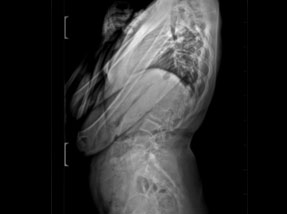

• Pre-Surgery

• Pre-SurgeryBefore

Case 1